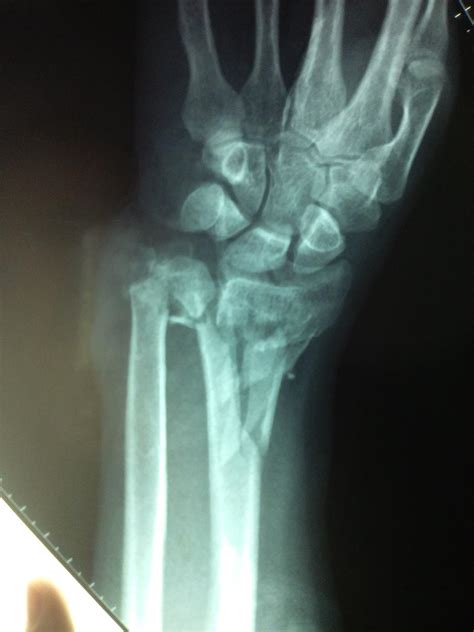

When you take a child to the emergency department for a suspected buckle fracture radius, the physician will perform a physical examination followed by an X-ray. It is important to note that because the fracture is a compression rather than a gap, it can sometimes be difficult to see on an X-ray unless the image is taken from exactly the right angle.

Radiologists look for a small "kink" or cortical disruption on the distal radius. Sometimes, a subtle thickening of the cortex is the only diagnostic clue. If the initial X-ray is inconclusive but the clinical suspicion remains high, doctors may recommend a follow-up visit or immobilization as a precautionary measure.